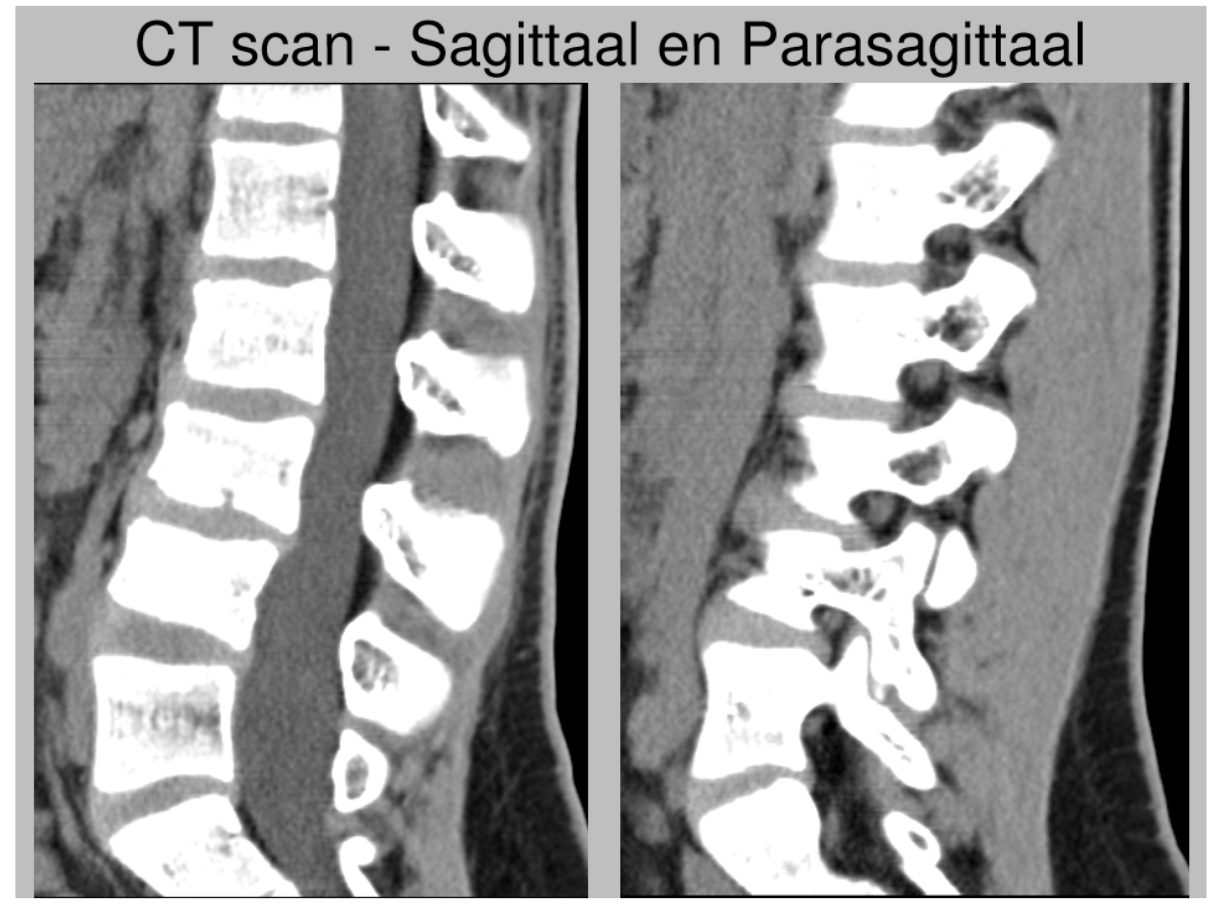

CT-scan: sagittaal & parasagittal

(medio)sagittaal = door het midden

parasagittaal = een beetje naar links of naar rechts